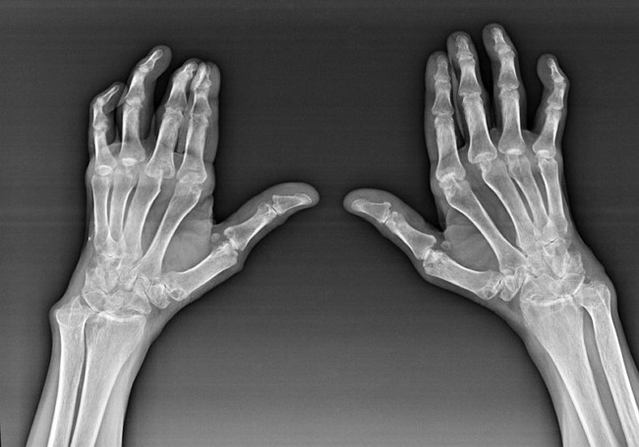

Rheumatoid arthritis

Rheumatoid Arthritis is a disease that the human immune system has damaged the body's own tissues.In other words, the Rheumatoid Arthrity is the pathology of autoimm.This disease is also systematic because many tissues are affected by him (Muscles, joints, veins, etc.) and bodies (Heart, kidneys, lungs, etc.) in the body.

Although there is a systematic disease at the bottom of the rheumatoid arthritis, the joints suffer, the lesion of other tissues and bodies are in the back plain.This disease can be affected by almost all sorts of brush joints (Wrist, carpal-paths, metacarpal-phalanx, phalanx combinations).The lesion is usually symmetrical (These are.The same joints are affected) Both acquisitions, swelling and damaged joints are painfully accompanied by pain.In the morning, while lifting out of the bed, there is a number of stiffness in affected joints that can last about 1 hour and then disappear.

Often with rheumatic arthritis near the affected joints of the brush (More piano-phalanx, phalanx combinations) Rheumatoid nodules appear.They are a round format located under the skin.In the brush, these forms arise in the back.They are in palpation, intense, inactive, painless.Their number can change.